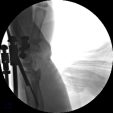

5.使用执行器夹持克氏针,于掌侧穿针,撬拨骨块并使用六轴机器人固定针末端以维持撬拨位置。

6.六轴机器人撬拨骨块过程